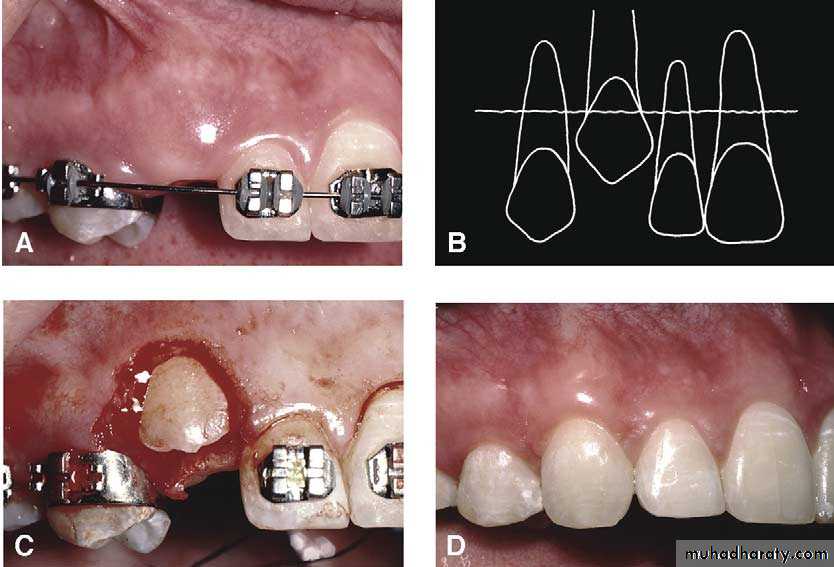

Surgical exposure :the path of eruption is not obstructed

Surgical exposure with orthodontic traction: the path of eruption is obstructed

Surgical exposure with orthodontic treatment (palatal approach )

The initial stage of the operation is to reflect the mucoperiosteum and to remove the bone overlying the tooth to expose the greatest coronal diameter, the incisal edge and the cingulum . before repositioning the palatal flap a window is excised in it corresponding to the bony cavity containing the crown .the flap is then sutured as usual and a pack of iodoform gauze should be pressed firmly in to the bony defect so as to cover the exposed crown .

Mosul university- College of dentistry-oral & maxillofacial surgery department

This pack should be held in position with suture and left insitu for 2-3 weeks to prevent granulation tissue and mucosa from overgrowing the denuded crown .after removal of the pack the progress of eruption should be observed at frequent intervals .

Following eruption of the tooth , orthodontic treatment may be required to guide it into a good position in the arch . Some times orthodontic traction is arranged at the time of surgery .